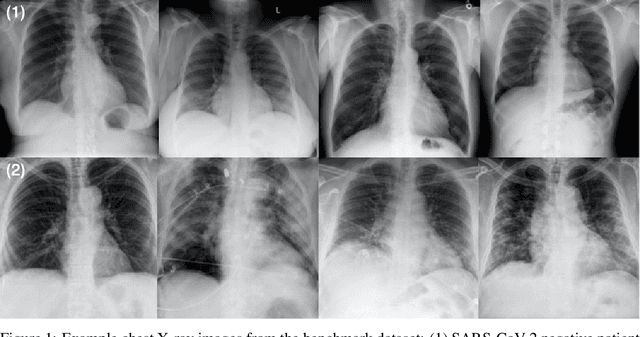

Abstract:As the COVID-19 pandemic continues to devastate globally, the use of chest X-ray (CXR) imaging as a complimentary screening strategy to RT-PCR testing continues to grow given its routine clinical use for respiratory complaint. As part of the COVID-Net open source initiative, we introduce COVID-Net CXR-2, an enhanced deep convolutional neural network design for COVID-19 detection from CXR images built using a greater quantity and diversity of patients than the original COVID-Net. To facilitate this, we also introduce a new benchmark dataset composed of 19,203 CXR images from a multinational cohort of 16,656 patients from at least 51 countries, making it the largest, most diverse COVID-19 CXR dataset in open access form. The COVID-Net CXR-2 network achieves sensitivity and positive predictive value of 95.5%/97.0%, respectively, and was audited in a transparent and responsible manner. Explainability-driven performance validation was used during auditing to gain deeper insights in its decision-making behaviour and to ensure clinically relevant factors are leveraged for improving trust in its usage. Radiologist validation was also conducted, where select cases were reviewed and reported on by two board-certified radiologists with over 10 and 19 years of experience, respectively, and showed that the critical factors leveraged by COVID-Net CXR-2 are consistent with radiologist interpretations. While not a production-ready solution, we hope the open-source, open-access release of COVID-Net CXR-2 and the respective CXR benchmark dataset will encourage researchers, clinical scientists, and citizen scientists to accelerate advancements and innovations in the fight against the pandemic.